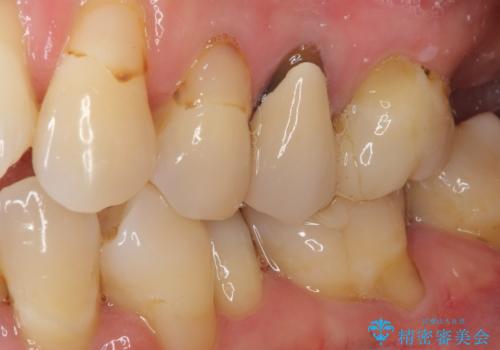

- 歯肉が退縮したためにクラウンの縁や歯根が見えてしまっていることを気にして来院された患者様です。

仮歯に変えた後にオールセラミッククラウンにて補綴することとしました。

強い咬合力や磨きすぎなどにより、歯根が見えてしまったり、金属の縁が見えてしまったりし、審美障害を引き起こすことがあります。

歯根が変色してしまうと、歯肉越しに歯根の黒い色が透けてしまうことがあり、この点についてはどうにも施しようがないため、患者様には事前のご理解いただきました。